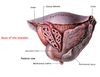

3: Crus

4: Bulb of the vestibule